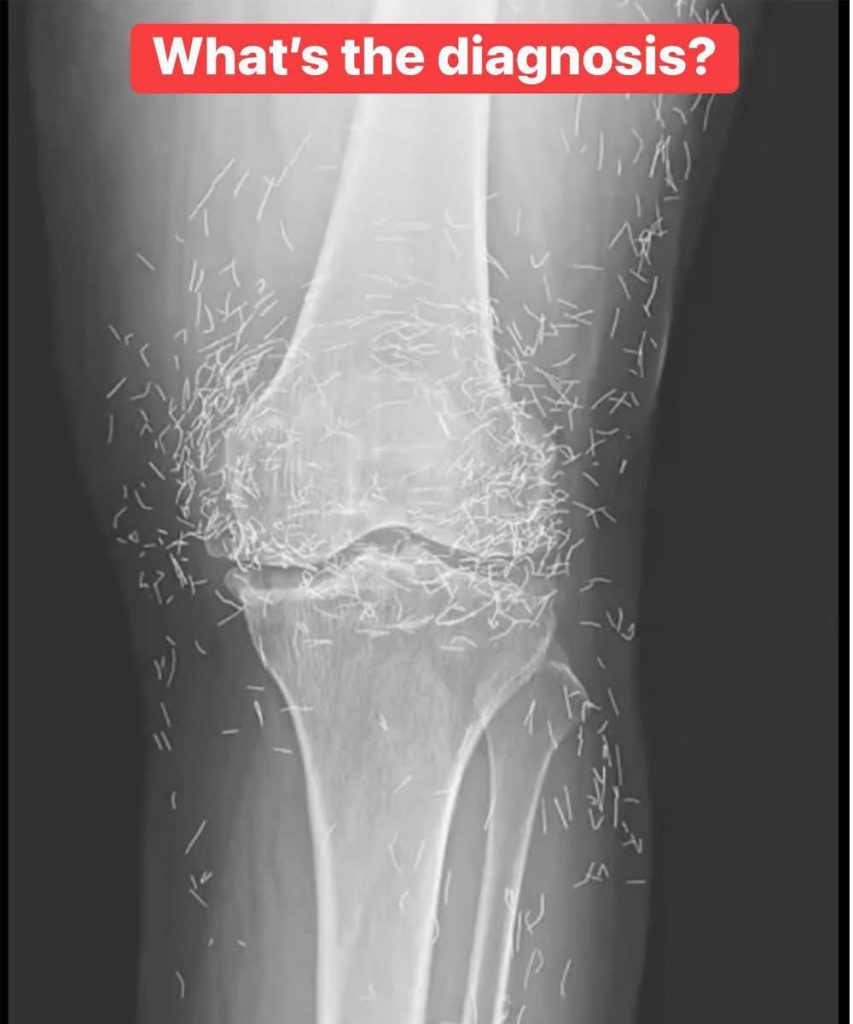

Upon reviewing an X-ray of an elderly woman’s painful knees, doctors made a startling discovery: her tissue contained hundreds of tiny, retained gold acupuncture needles. The 65-year-old patient from South Korea suffered from osteoarthritis and had sought acupuncture after conventional pain medication proved ineffective and caused stomach issues.

Retained needles can also complicate medical imaging. They may obscure anatomical details on an X-ray, making accurate diagnosis more challenging.

The body naturally attempts to isolate foreign objects through inflammatory responses and the formation of fibrous tissue. Additionally, retained metal needles can prevent patients from undergoing MRI scans due to the risk of movement and potential damage to nearby arteries.